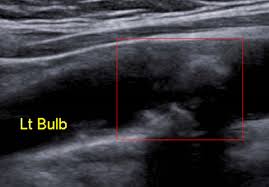

경동맥 초음파 검사란, 초음파 장비를 사용하여 목 부위의 경동맥 상태를 실시간으로 검사하는 방법입니다. 이 검사는 주로 경동맥의 혈류 속도, 혈관의 두께, 그리고 플라크의 존재 여부를 평가하여, 경동맥 초음파 검사로 알 수 있는 병을 진단합니다. 검사 과정은 매우 간단하며, 환자는 편안한 자세로 누운 상태에서 초음파 탐촉자를 목 부위에 대고 진행됩니다. 일반적으로 검사 시간은 10~15분 정도 소요되며, 검사 후 당일에 결과를 확인할 수 있어 빠른 조치가 가능합니다.

경동맥 죽상경화증은 경동맥의 벽에 콜레스테롤이나 칼슘이 침착되어 두꺼워지는 병입니다. 경동맥 초음파 검사로 알 수 있

는 병 중 가장 흔한 질환으로, 경동맥의 내중막 두께(IMT)를 측정하여 동맥경화증의 진행 여부를 판단할 수 있습니다. IMT가 1mm 이상이면 동맥경화가 진행되고 있다는 것을 의미합니다. 이 질환은 뇌졸중의 위험 요소로 작용하므로 조기 진단이 중요합니다.